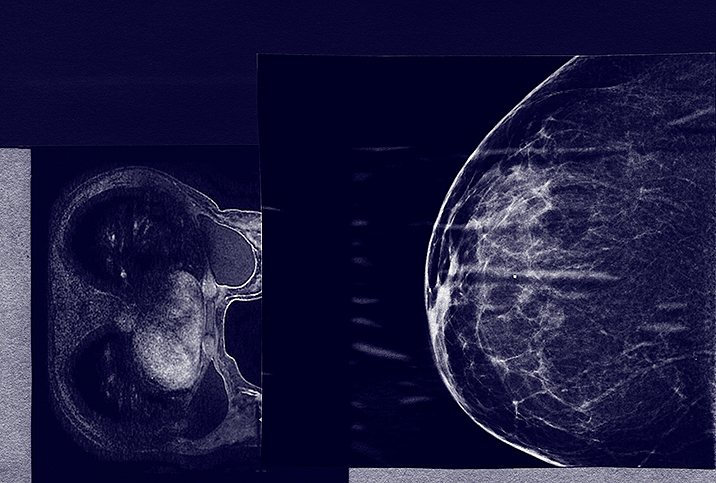

Dense breasts can obscure mammograms and raise breast cancer risk.

Dense tissue can put women at a higher risk for breast cancer over the course of their lives.

Are your breasts high or low density? Here's what you need to know.

Misconceptions about breast density abound, so it’s important to know the facts.

Breast density may not affect a woman’s day-to-day life, but it can correlate to breast cancer.